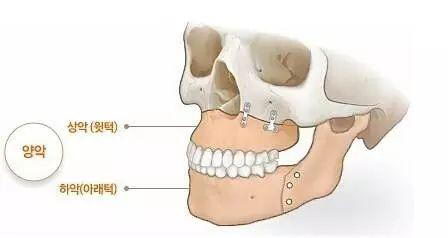

双鄂=上颚(上颌骨)+下颚(下颌骨)

(图中带颜色部位)

▲图片来自《3Dbody》

▲双鄂手术方式示意图